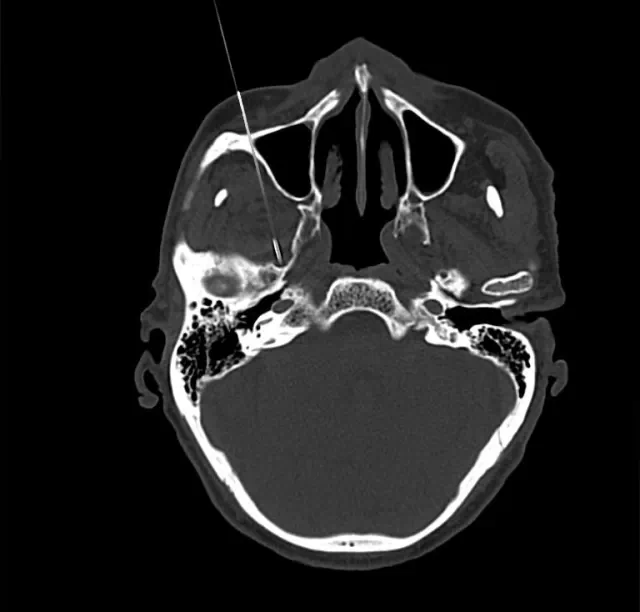

(二)四川奥斯迪康骨医院治疗方法:CT引导射频热凝术

治疗原理:三叉神经为感觉神经,其中神经纤维(AA纤维和AB纤维)能耐受较高温度,而痛觉神经纤维不能耐高温,CT引导三叉神经热凝术选择破坏痛觉纤维,使患者疼痛治愈。